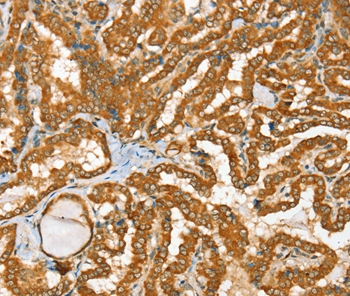

Immunohistochemical analysis of paraffin-embedded Human thyroid cancer tissue using #36712 at dilution 1/25.